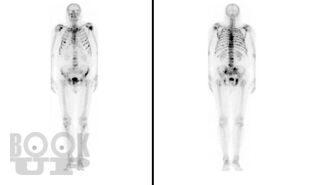

Метастазы в костную ткань у пациентов при онкоурологической патологии

Учебное пособие подготовлено в соответствии с требованиями ФГОС ВО 3++ по программе подготовки кадров высшей квалификации в ординатуре по специальности 31.08.68 Урология (2014). В пособии на современном уровне излагаются механизмы распространения метастазов в костную ткань, их диагностика и лечение у пациентов с онкоурологической патологией. Пособие содержит рисунки из открытых источников интернета.